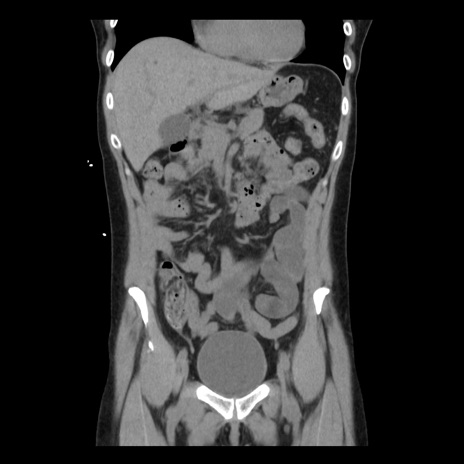

症例10(冠状断像)

【症例】 50歳代女性

【主訴】 腹痛

【現病歴】前日生レバーを食べた。今朝に排便あり。 昼前に突然発症の腹痛を生じ、当院救急外来を受診した。

【既往歴】 子宮筋腫にてで子宮全摘後

【身体所見】 意識清明、腹部:平坦、軟、下腹部やや左を中心に圧痛・反跳痛あり、筋性防御あり

【データ】WBC 7800、CRP 0.07